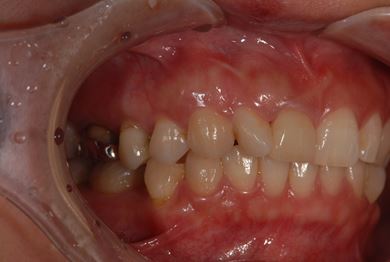

| 性別/年齢 | 女性 / 38歳 | ||||||||||||||||||||||||||||||||

| 主訴 | 右奥歯2本、インレーの相談をしたい。 | ||||||||||||||||||||||||||||||||

| 治療方針 | セラミック治療にて、審美的回復を行う。 | ||||||||||||||||||||||||||||||||

| 治療内容 | ハイブリッドセラミックインレー2本、メタルボンドセラミッククラウン2本(メタルボンド用土台2本)、オールセラミッククラウン1本(オールセラミック用土台1本) | ||||||||||||||||||||||||||||||||

| 総治療費 | 495,758円 | ||||||||||||||||||||||||||||||||

| 治療期間 | 1年6ヶ月 |